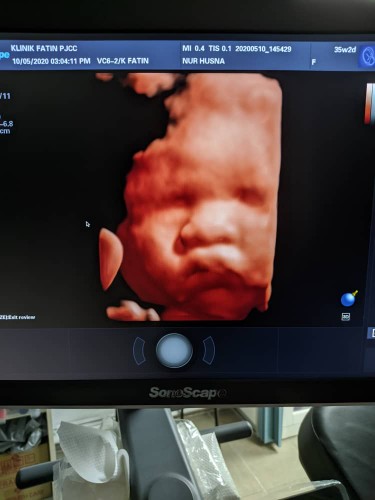

olla mommies.. heeheee.. dokter scan pon geram tengok awak.. pipi gebu sangat.. mulut muncung sebab kena kacau masa tidor.. dokter tolak2 sebab tak nampak muka.. pergi tutup muka tak nak d kacau.. haahaaa.. papa kata muka papa la.. ermm takpe la mama donate pipi je kat awak.. sekarang dah 2.7kg, terlebih dari yg dokter estimate.. takot nanti cukup 40w awak dah 3.8kg.. mama kena jaga makan la jawab nye ni.......... hb pon payah naik.. semoga semua berjalan lancar hendakNya.. mama dah mula sakit tulang miss v belah kiri.. kaki mula bengkak.. ?